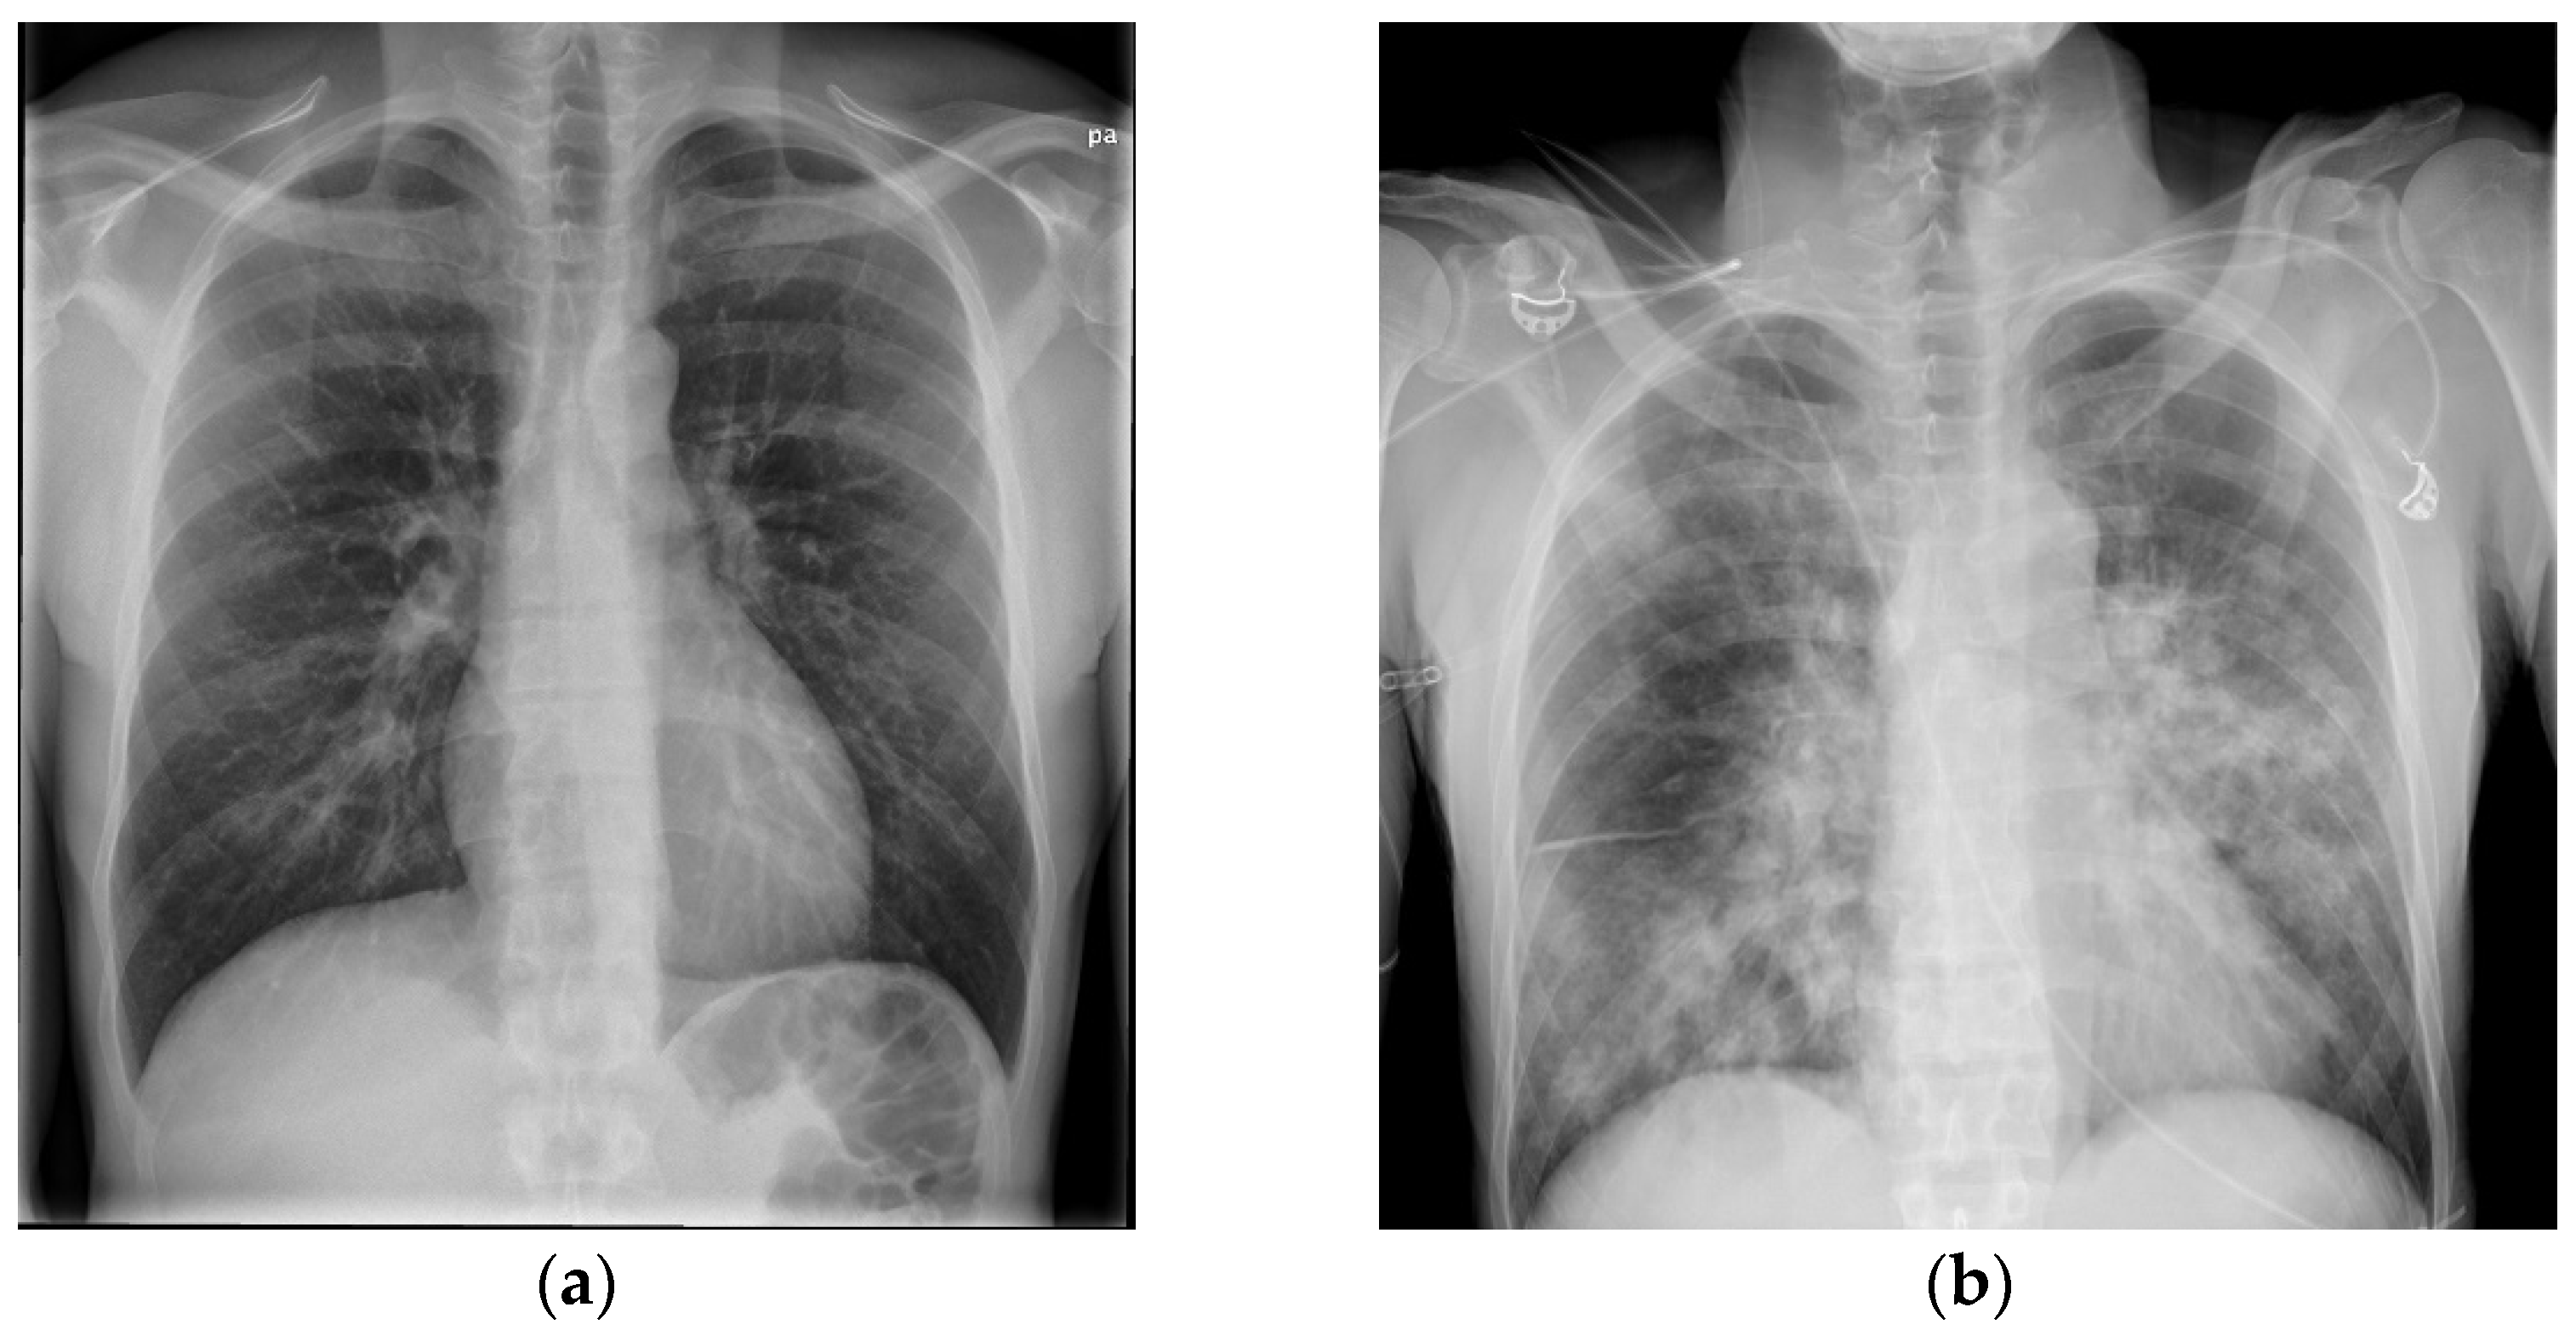

After 13 weeks of hospitalization in total, he was discharged with home oxygen therapy and offered rehabilitation. Five months later, he did not need home oxygen therapy but was still limited in his daily life because of troubled and wheezing breathing. A spirometry showed severely reduced lung capacity with a forced vital capacity (FVC) of 2.56 L (51.5% of the expected capacity) and signs of emphysema and obstruction. A CT scan of the chest showed bilateral pulmonal cysts, bronchiectasis, consolidation, and dilation of the trachea (Figure 3). Scanning in the expiratory phase showed an almost complete collapse of the trachea and comprehensive air trapping, and he was diagnosed with tracheomalacia. Now, 4 years later, the patient is still followed in the Pulmonology Out-Patient Clinic at the National Hospital of the Faroe Islands. One and a half years after discharge, he was examined at a German thorax clinic to find out if he could benefit from a tracheal stent implantation, but an indication was not found. He now receives intermittent continuous positive airway therapy (CPAP), regular pneumococci, influenza vaccinations, and prophylactic antibiotics.

Figure 3. (a,b) CT scan of the chest with coronal reconstruction, showing bilateral pulmonal cysts, bronchiectasis, consolidation and dilation of the trachea, 5 months after admission.